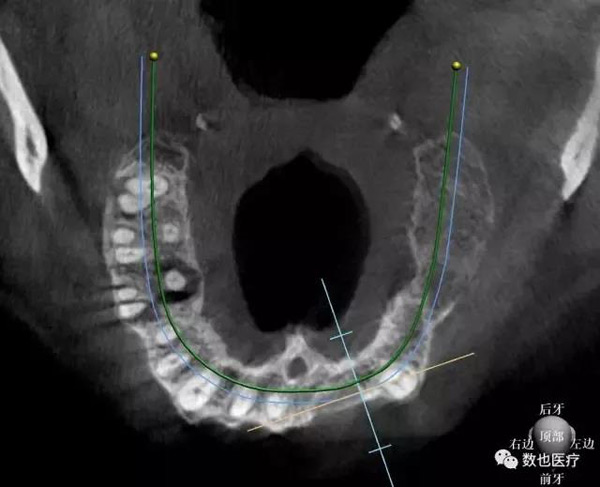

患者上颌骨条件较差,拔牙后存在较多的拔牙窝。考虑做即刻修复需要较好的初期稳定性,根据患者颌骨情况,计划种植6颗cortex种植体,避开骨缺损区域,远中两颗倾斜避开上颌窦。